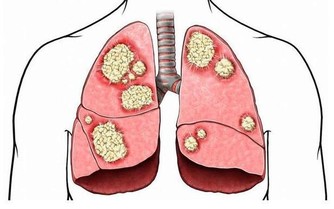

除此之外,常見的還有痛風、肥胖、風濕性關節炎以及類風濕性關節炎等都會引起“膝蓋”疼,由此可見,我們需要對此引起高度的重視,做到“早發現,早治療”,防止由於個人忽視導致疾病逐漸加重、惡化,進而對家庭和日常生活產生不良影響。